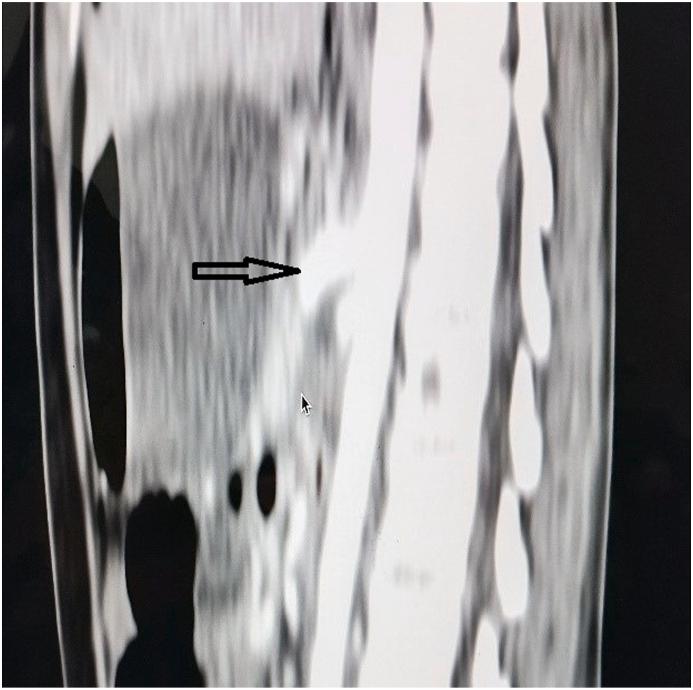

根治性肾切除及腹膜后淋巴结清扫术后肠系膜上动脉损伤中“侧支循环是救星”

Superior Mesenteric Artery (SMA) during renal surgery is rarely reported but potentially devastating complication. It can rarely occur in patients with distorted vascular anatomy like in large left renal tumors with vascular infiltration and bulky lymphadenopathy, or in the setting of re-do surgery with extensive scarring. Failure to recognize and repair an SMA injury may result in ischemic bowel and consequently high mortality. Herein, we present a case scenario of injury to the SMA during radical nephrectomy missed intraoperatively and managed conservatively in the post-operative period in view of collateral circulation to the gut.

肾手术期间肠系膜上动脉(SMA)损伤鲜有报道,但却是一种潜在的灾难性并发症。它很少发生在血管解剖结构扭曲的患者中,如伴有血管浸润和大量淋巴结病的巨大左肾肿瘤患者,或在有广泛瘢痕形成的再次手术情况下。未能识别和修复SMA损伤可能导致肠缺血,进而导致高死亡率。在此,我们介绍一例根治性肾切除术期间SMA损伤的病例,术中未发现,鉴于肠道的侧支循环,术后采取保守治疗。